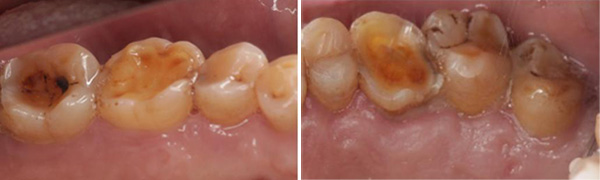

牙本质敏感症(Dentin Hypersensitivity,DH)是指牙齿受到机械、温度、化学等生理范围内的刺激时出现的短暂、尖锐的疼痛或不适现象,且随着刺激去除迅速消失。这种典型症状主要是由于磨耗、磨损等多种生理或病理原因导致釉质的完整性受到破坏,从而使牙本质小管直接开放于口腔环境中所致,是口腔门诊常见的一种牙体硬组织非龋性疾病。

1、磨损:不正确的口腔卫生措施,包括刷牙力量过大、使用硬质刷毛牙刷、高频率刷牙或延长刷牙时间等与牙本质敏感有重要关系。进食酸性食物和饮料后即刻刷牙可能刷除脱矿软化的牙体表面硬组织。使用高摩擦值的牙膏可加重牙釉质和牙本质的磨损。

2、磨耗:牙体磨耗包括异常的咬合状况、夜磨牙症等。

3、酸蚀:酸蚀作用包括外源性酸和内源性酸。外源性酸主要来源于酸性食物、饮料、药物(如维生素C、阿司匹林)以及工作环境(如电池工业车间、氯制剂消毒的游泳池等);内源性酸来源于胃食管反流、妊娠反应等情况下的胃酸。